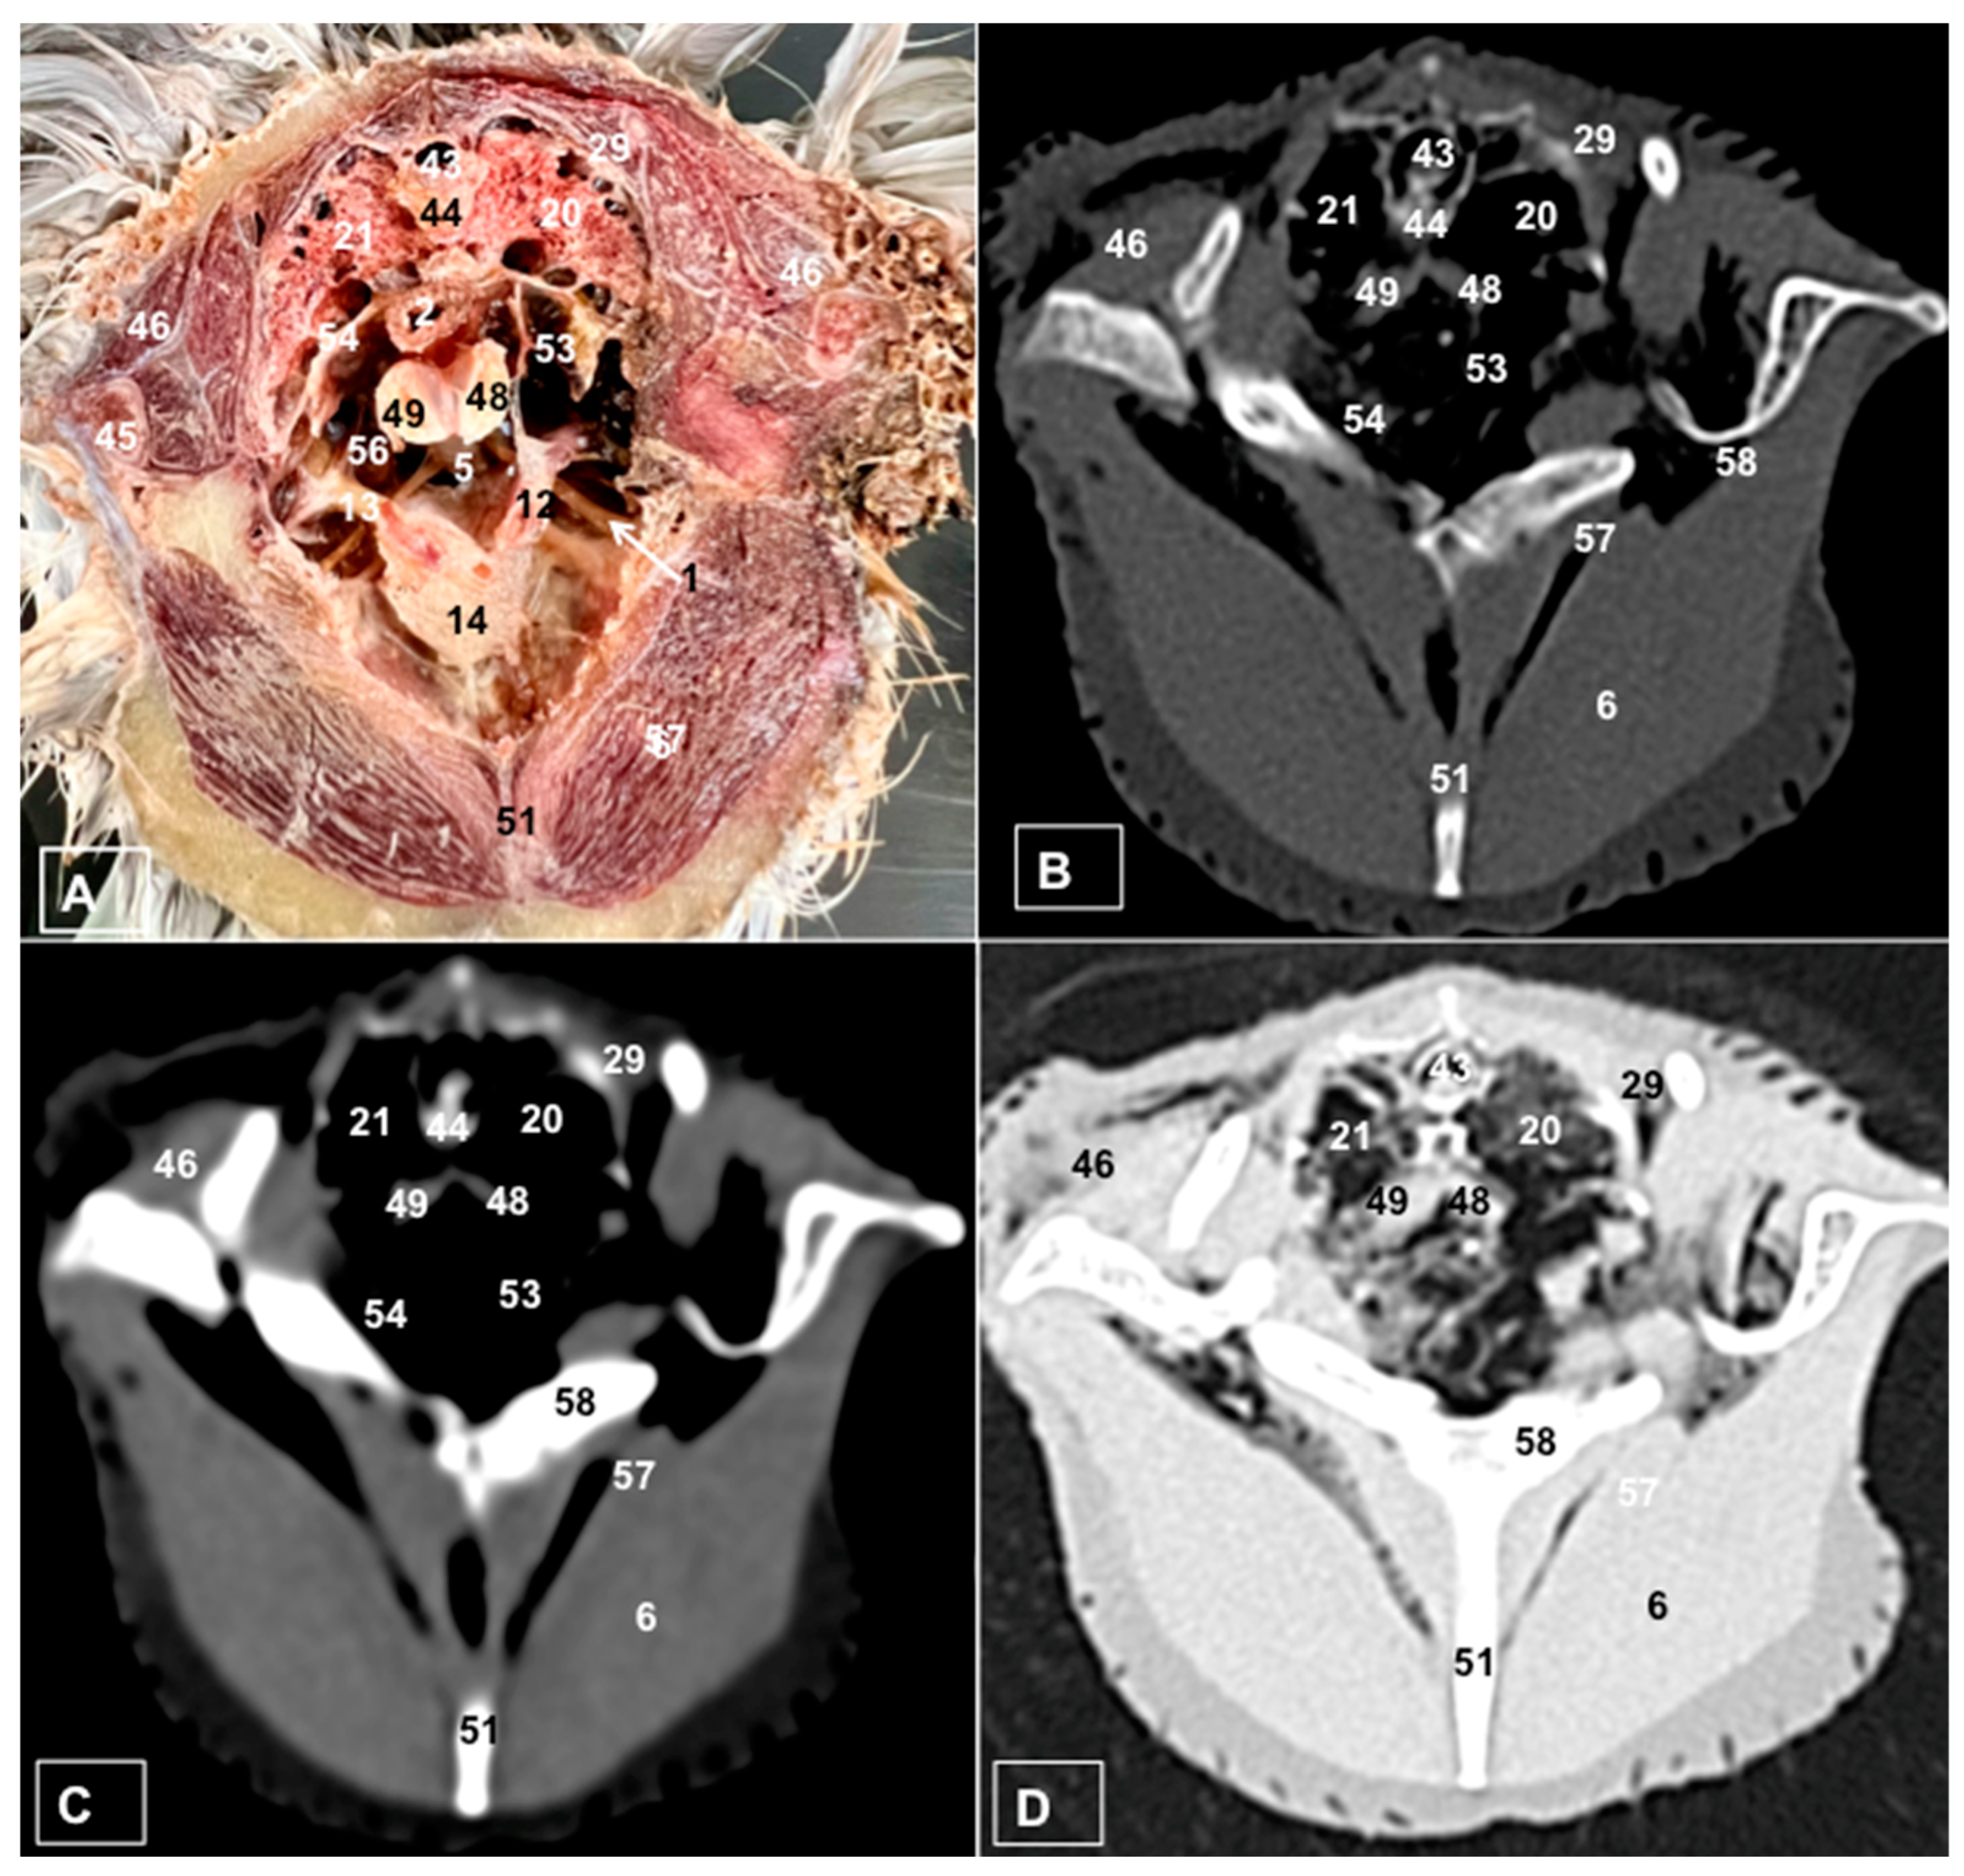

A Cadaveric Study Using Anatomical Cross-Section and Computed Tomography for the Coelomic Cavity in Juvenile Cory’s Shearwater (Aves, Procellariidae, Calonectris borealis)

3. Results

3.1. Anatomical Dissections and Cross-Sections

3.2. Computed Tomography Images